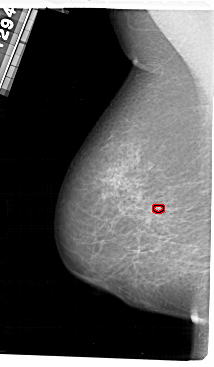

A_1637_1.LEFT_MLO

LEFT_MLO LINES 5491 PIXELS_PER_LINE 3196 BITS_PER_PIXEL 12 RESOLUTION 43.5 OVERLAY

FILE: A_1637_1.LEFT_MLO.OVERLAY

TOTAL_ABNORMALITIES 1

ABNORMALITY 1

LESION_TYPE CALCIFICATION TYPE PLEOMORPHIC DISTRIBUTION CLUSTERED

ASSESSMENT 4

SUBTLETY 1

PATHOLOGY MALIGNANT

TOTAL_OUTLINES 1

BOUNDARY